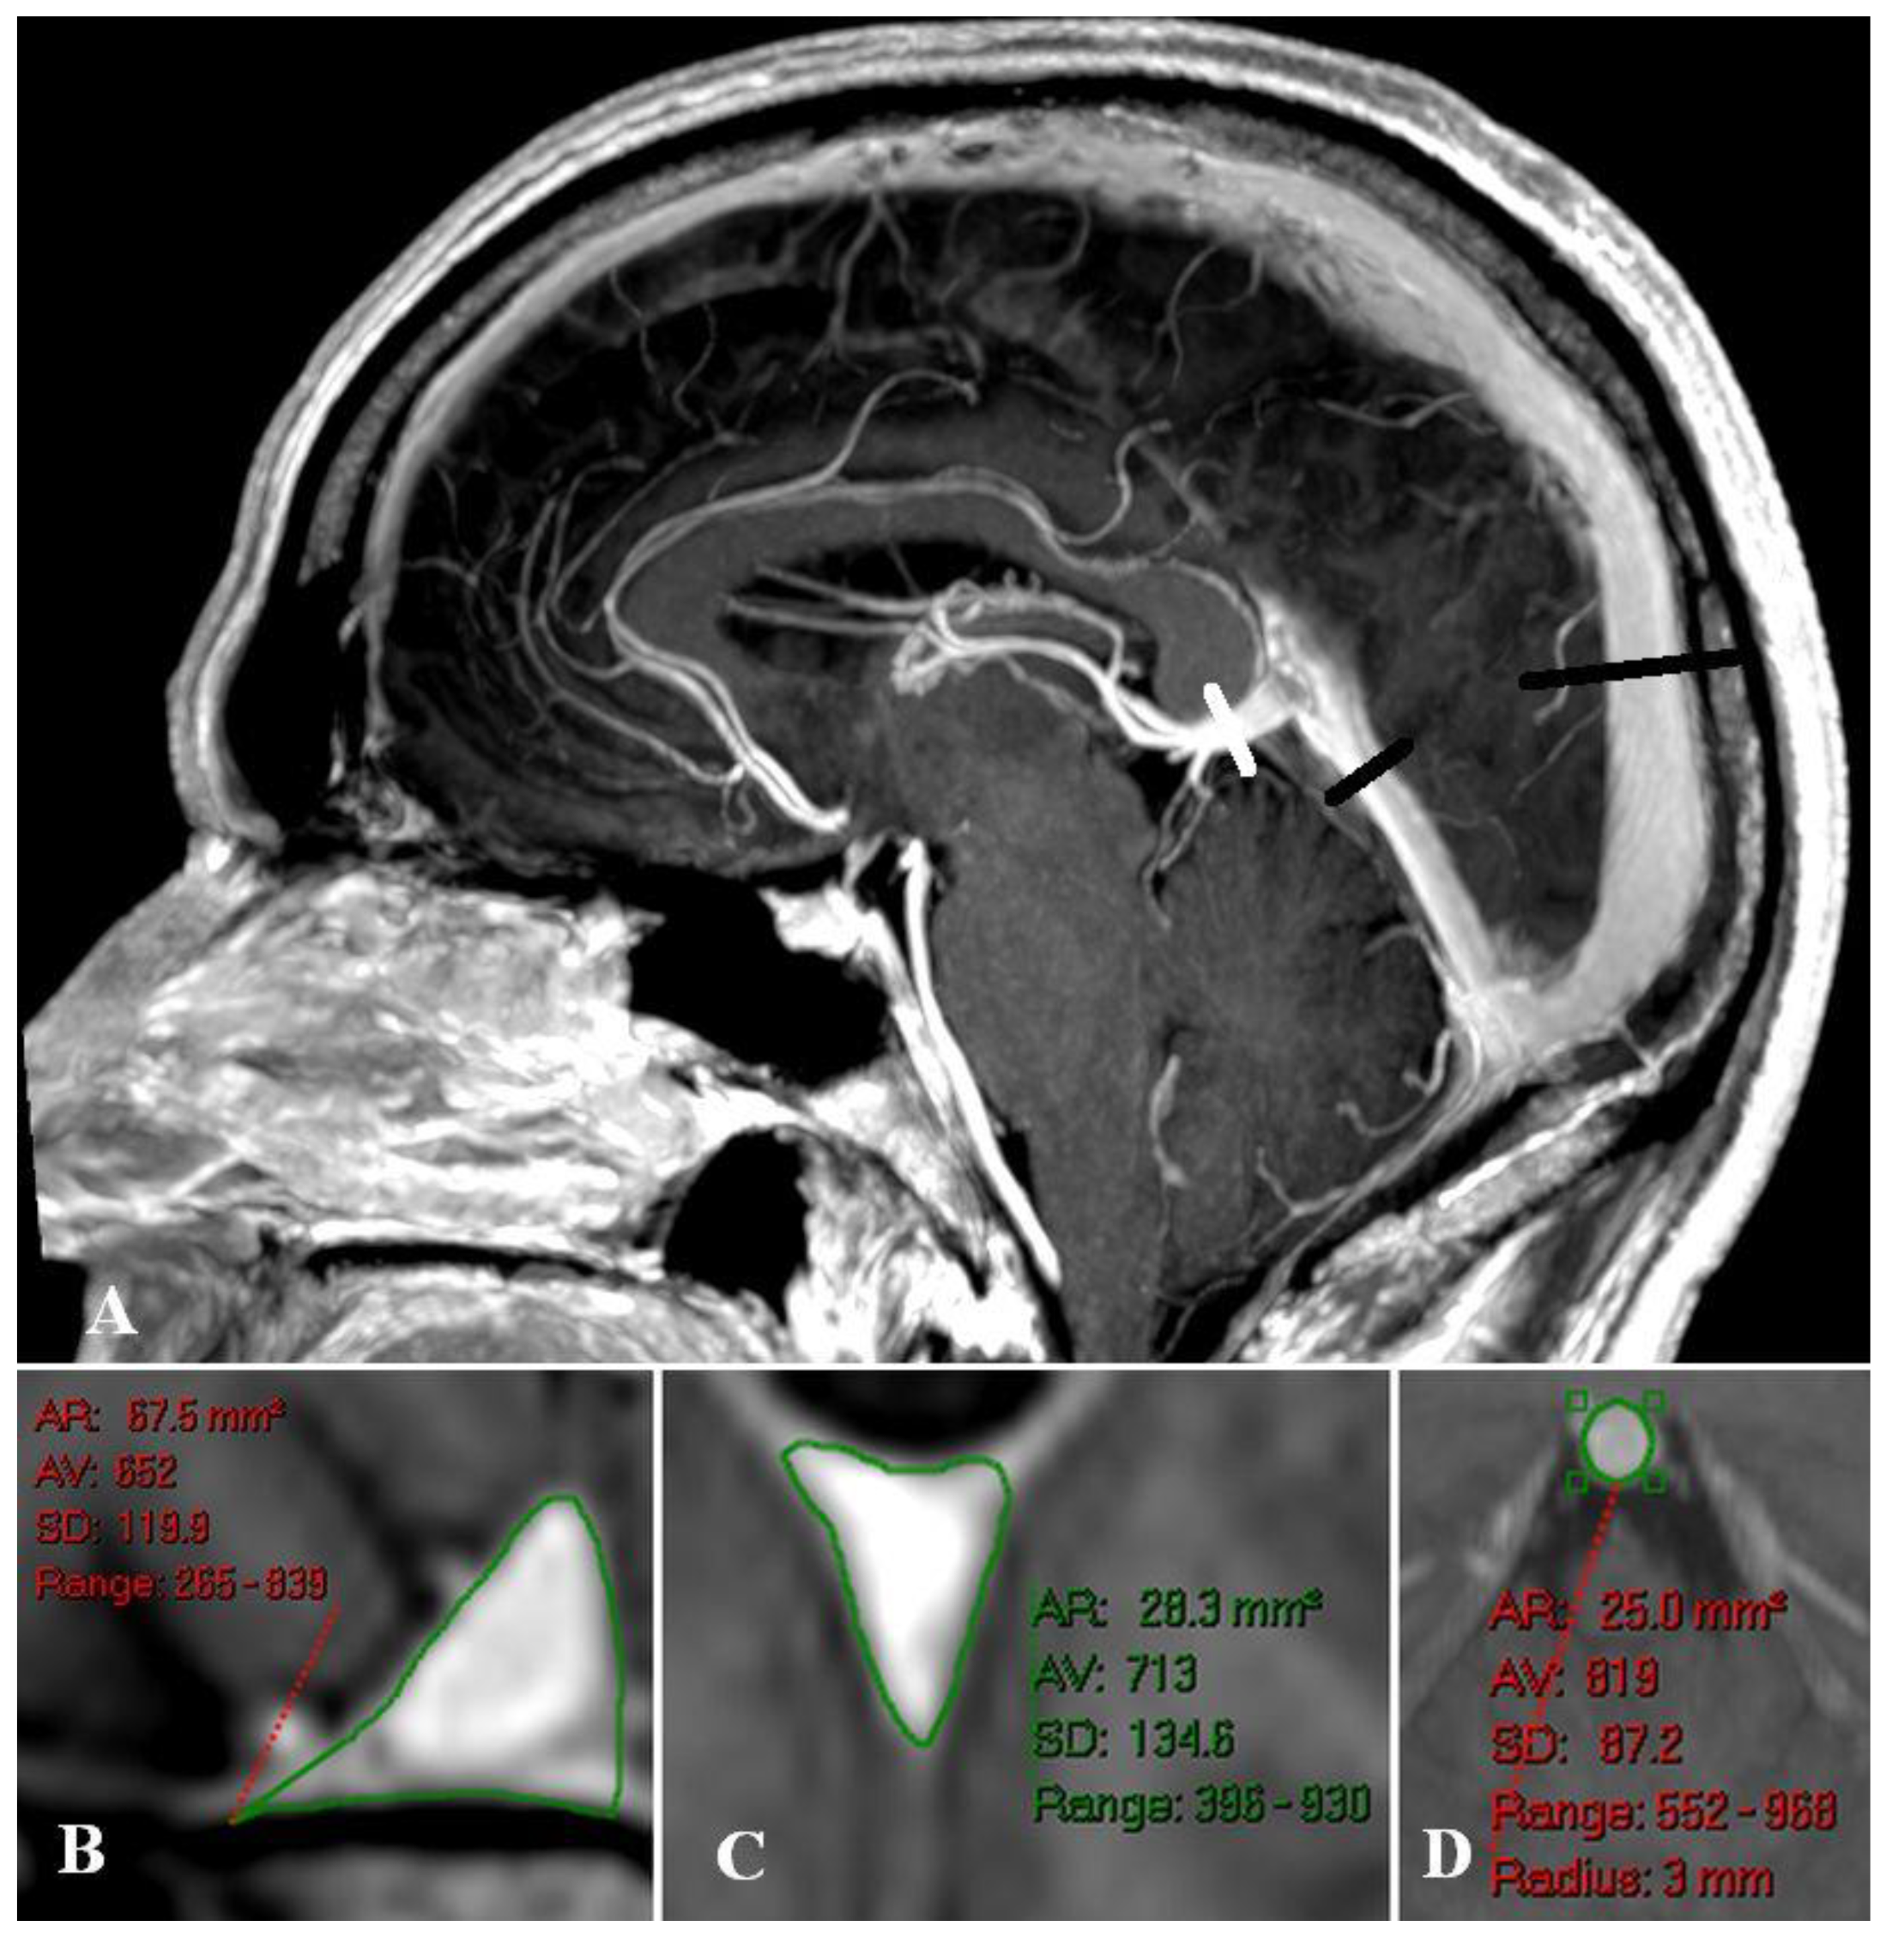

Sagittal and straight sinus dilatation

Bridging vein dilatation